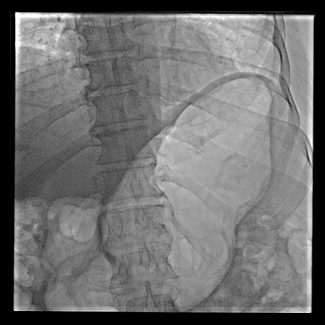

Masashi Yokoi, MD; Tsuyoshi Ito, MD; Junki Yamamoto, MD; Yoshihiro Seo, MD

A 79-year-old man with the diagnosis of acute myocardial infarction complicating cardiogenic shock received Impella CP (Abiomed) insertion via a femoral approach.